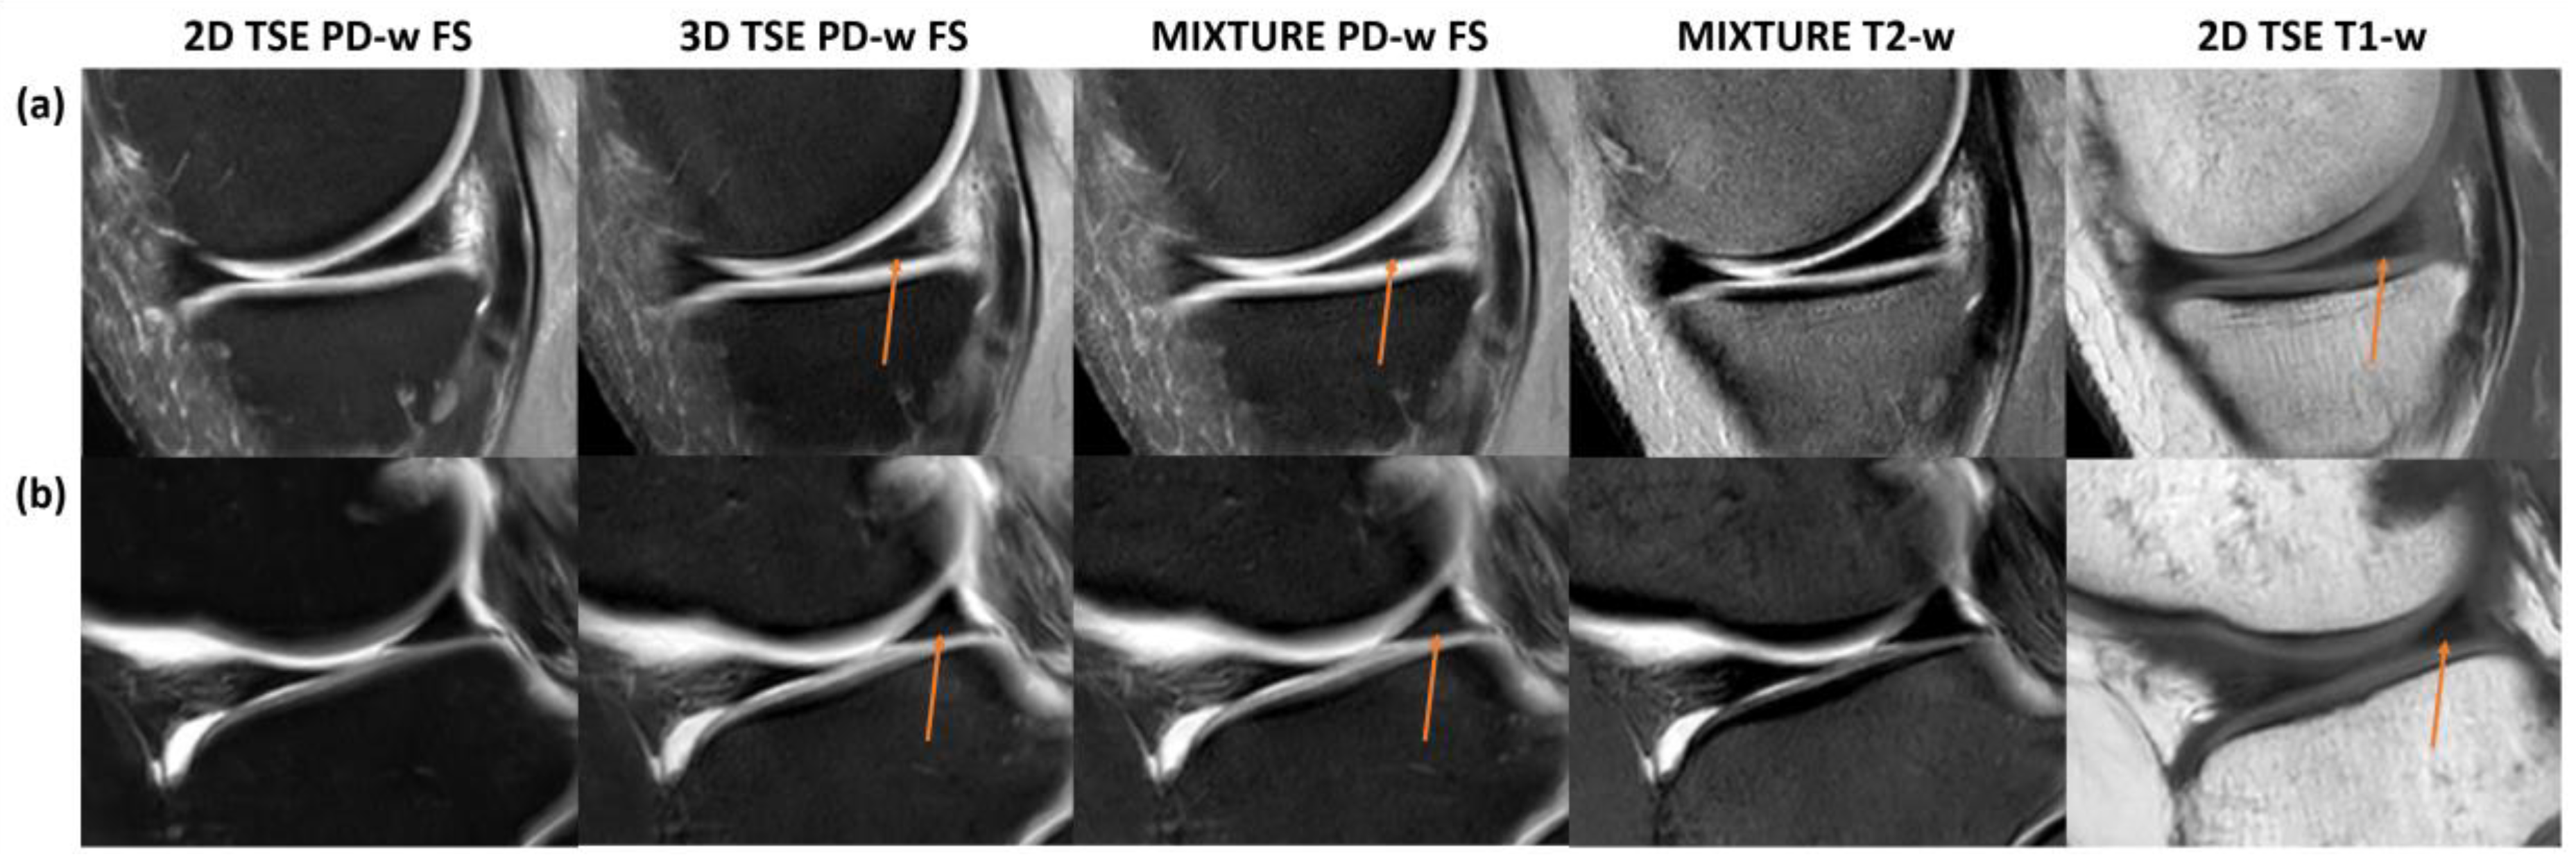

3.6. Artificial Findings in Two Meniscal Posterior Horns

In two knee joint specimens, artificial findings of the meniscal posterior horns were noted for the MIXTURE and 3D TSE sequences, i.e., a fine hyperintense line extending from the meniscus base to the red–white zone that may principally be mistaken as a tear and a hyperintense area toward the meniscal undersurface that could be mistaken as degenerative meniscopathy. We consider these signal alterations artificial because they were absent in the corresponding 2D TSE and MIXTURE T2-weighted sequences (Figure 5). Yet, correlates were visible on the respective T1-w images.

Figure 5. Artificial findings in the meniscal posterior horn. Fine linear structures of high signal intensity and variable size in the posterior horns of the medial (a) and lateral (b) meniscus (orange arrows) were only appreciable on the 3D TSE and MIXTURE PD-w FS images but not on the corresponding 2D TSE or MIXTURE T2-w images. These findings are likely artificial because of the missing correlate on the T2-w image. The hyperintense structural correlate on the T1-w images suggests that the 3D TSE and MIXTURE PD-w FS images depict residual T1 contrast, which can be due to the shorter relaxation times and the utilization of complex refocusing patterns compared to the 2D TSE PD-w FS sequence. The latter had a longer TR, increasing the likelihood of complete T1 relaxation.